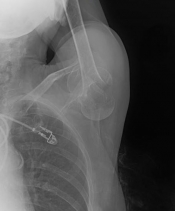

What’s the Diagnosis? Gepost op 2 januari 20202 januari 2020 door netwerkvsseh What’s the Diagnosis? @emdaily.cooperhealth.org Dit delen: Delen op X (Opent in een nieuw venster) X Share op Facebook (Opent in een nieuw venster) Facebook Delen op LinkedIn (Opent in een nieuw venster) LinkedIn E-mail een link naar een vriend (Opent in een nieuw venster) E-mail Afdrukken (Opent in een nieuw venster) Print Vind-ik-leuk Aan het laden... Gerelateerd